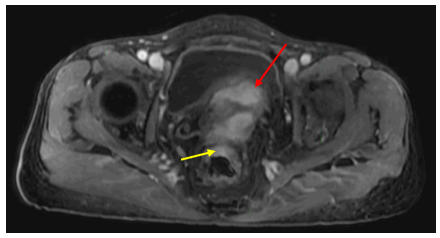

MRI tiểu khung:

Hình 5: Vị trí cạnh đáy tử cung hai bên có các đám ngấm thuốc mạnh, lớn nhất kích thước 18x19mm, ranh giới không rõ với lớp cơ ngoài tử cung và các quai ruột lân cận (mũi tên đỏ). Trực tràng xẹp, hạn chế đánh giá,sơ bộ thấy dày nhẹ thành trước trực tràng cao, dày nhất 7mm, trên đoạn dài 50mm, tăng ngấm thuốc nhẹ sau tiêm, không thấy mất cấu trúc lớp, không thấy thâm nhiễm ngoài thành (mũi tên vàng).

Hình 6: Nhiều dịch tự do ổ bụng, dày nhất do được ở tiểu khung ~35mm (mũi tên đỏ). Dày phúc mạc lan tỏa (mũi tên vàng).